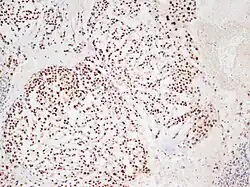

In 2015 the first consensus guidelines for the diagnosis and treatment of chordoma were published in The Lancet Oncology.[13] These tumors express brachyury and cytokeratin, which can be detected by immunohistochemistry.

There are three histological variants of chordoma: conventional,[14] chondroid and dedifferentiated.

- The histological appearance of classical chordoma is of a lobulated tumor composed of groups of cells separated by fibrous septa. The cells have small round nuclei and abundant vacuolated cytoplasm, sometimes described as "physaliferous" because of their cytoplasmic vacuoles, and their resemblance to the physalis plant.